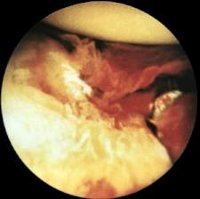

Наиболее информативным методом диагностики пигментного виллонодулярного синовита является артроскопия. Она позволяет увидеть утолщение и темно-розовое окрашивание синовиальной оболочки, растущие в полость сустава бурые ворсинчатые и узловые выросты, свободно расположенные оторвавшиеся узлы и ворсины, потемневшие суставные хрящи. Бурая и розовая окраска синовиальной оболочки, а также потемнение хрящей связаны с их геморрагическим пропитыванием и отложением гемосидерина. В ходе артроскопии берут биопсию синовиальной оболочки. Гистологическое исследование материала у пациентов с пигментным виллонодулярным синовитом выявляет узловую пролиферацию, наличие отложений гемосидерина и многоядерные гигантские клетки.